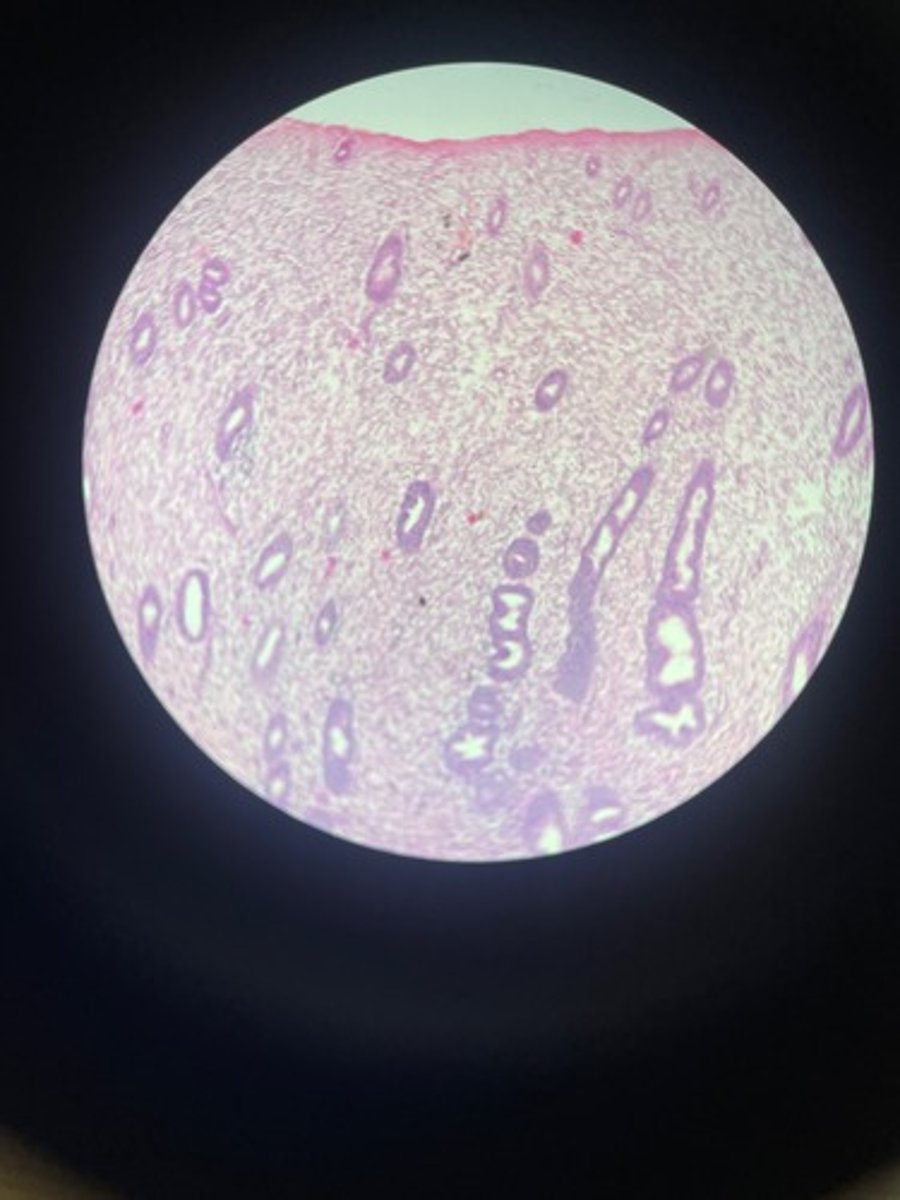

Ureter HE

Ureter HE

Ureter HE

Ureter HE

Ureter HE